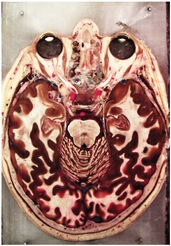

Table 2, Table 3, Table 4 and Table 5 present the results obtained through the multi-objective optimization image enhancement approach. Specifically, Table 2 and Table 3 show the results for natural images, while Table 4 and Table 5 display medical images. The tables are organized as follows: the first and second columns list the image names and their corresponding original, unenhanced versions. The third to fifth columns showcase the selected points from the Pareto front, representing the maximum contrast, knee point, and maximum detail, in that order. The final column illustrates the obtained Pareto front through the optimization process, with red, green, and orange points indicating the images that achieved maximum contrast, knee point, and maximum detail, respectively.

Table 4.

Medical image results—1.

Table 5.

Medical image results—2.

As observed in the results, the images extracted from the Pareto front significantly maximize contrast and detail compared to the original images. In all study cases, the original image is dominated by the solutions extracted from the fronts, demonstrating the approach’s effectiveness in improving visual quality. However, the differences among the three enhanced images for each problem require a more detailed analysis.

For medical images, there are instances where differences are more perceptible. For example, in the Medical3 image, the maximum contrast solution makes it difficult to visualize the internal details of the basophil (a white blood cell highlighted in the box), which could result in a less accurate interpretation. In contrast, the knee and maximum detail solutions provide a clearer view of the interior of the white blood cell. Similarly, in the Medical5 image, the maximum contrast solution highlights the hand and arm bone structures. However, the maximum detail image offers a more precise view of the internal structures within the bones (see the highlighted region), which is crucial for a more detailed evaluation. Another notable example is the Medical8 image, where the maximum detail solution offers a more detailed view of the internal structure of the eosinophil (another type of white blood cell). However, the maximum contrast image improves the visibility of red blood cells. As shown in the yellow box, this solution reveals a red blood cell that is nearly imperceptible in the other solutions. An interesting case is the Medical6 image, where only a few non-dominated solutions are present on the Pareto front. Despite the similarities among the preferred solutions, the nodules are much more perceptible in the enhanced images than in the original image, as observed in the highlighted region.